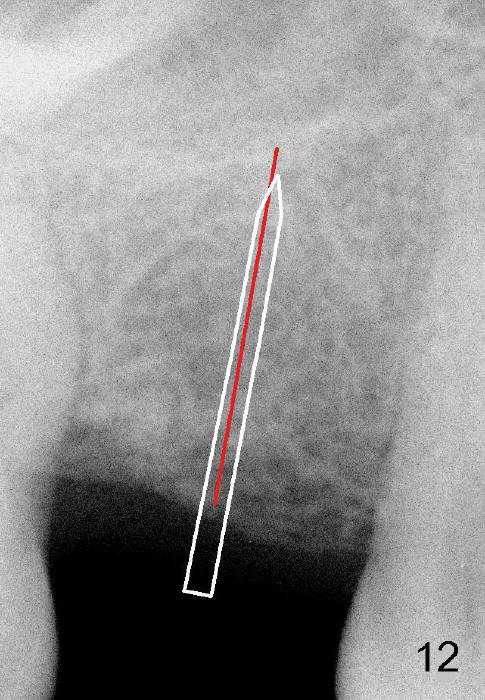

Another drawback of the implant placement is that the trajectory is off and distal (Fig.3-6), probably due to the low bone density in the distal aspect of the socket prior to extraction (Fig.7 CT sagittal section; MB: mesiobuccal root). The pilot drill must inadvertently have drifted distally and to the less dense bone (Fig.8). If it had been found, it could have been corrected early (Fig.9 red arrow). The trajectory could have been corrected immediately after the 2.6 mm expander (Fig.10). Ideally the pilot drill (Fig.11arrow) should be placed slightly mesial to the presumably mid edentulous line (red line) and only half of the length. If the trajectory is right, continue osteotomy (Fig.12). If not, correct it immediately.